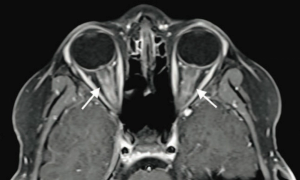

A 9-year-old boy with no significant medical history presented to the emergency department with 2 days of painless blurry vision. What's the diagnosis?